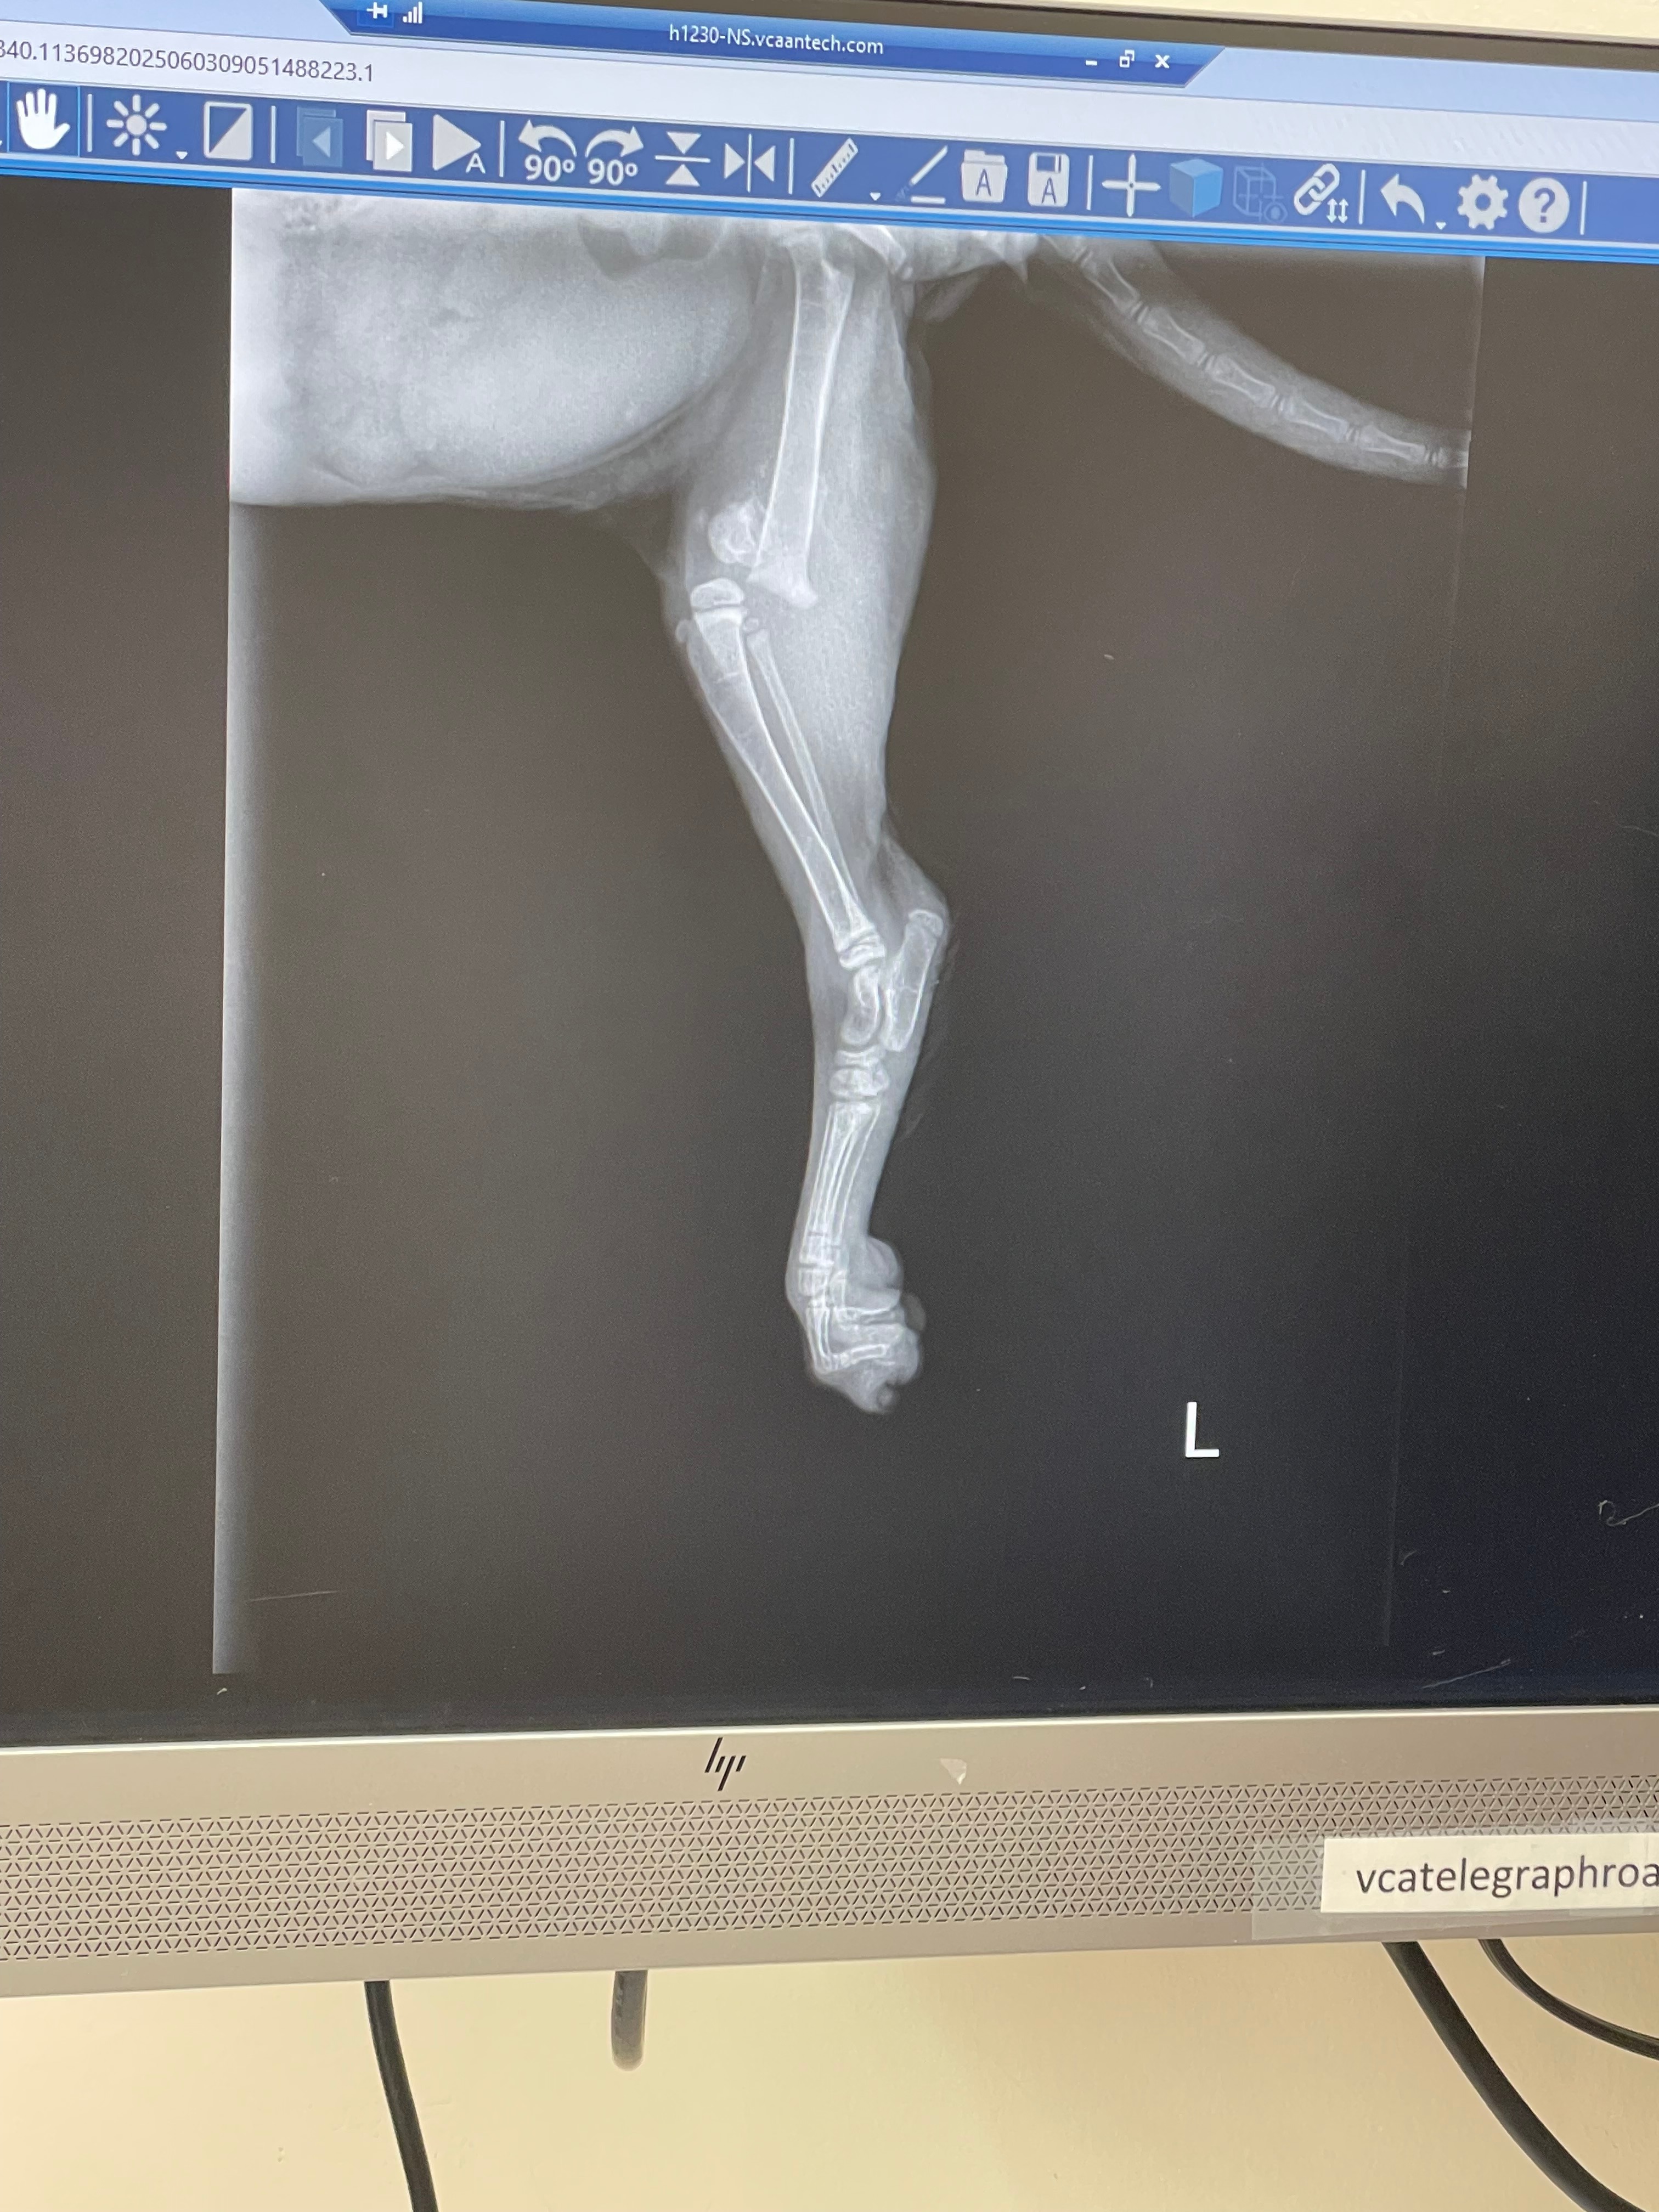

Now, this last week during our routine physical therapy to help improve her mobility, I realized I could not move and rotate her back left leg anymore. After a visit to the vet, it turns out she has broken her leg at the growth plate. The vet has recommended the amputation of her back left leg. After we heard this, we decided to keep her permanently to ensure she gets the best love and care she can.